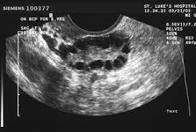

基礎濾泡應用於卵巢功能不佳病患不受月經週期影響

• 基礎濾泡可於試管嬰兒施行前數月評估

• 其施行時機不受月經不同週期明顯影響

• 其評估卵巢功能準確性類似Antimüllerian hormone (AMH)

The predictive value of antral follicle count remains unchanged across the menstrual cycle.

To explore whether the predictive value of antral follicle count (AFC) changes when measured at different times during the menstrual cycle. Antimüllerian hormone (AMH) and AFC are considered to be equally predictive of poor ovarian response; however, AMH is considered to have an advantage over AFC, because AMH concentrations can be measured at any time during the menstrual cycle.

A total of 3,117 patients with a transvaginal ultrasound within 3 months before their first IVF cycle.

Receiver operating curves (ROCs) were constructed for AFC as a screening test for poor ovarian response (fewer than four eggs collected). The areas under the curve (AUCs) were compared for ROCs from patients at different phases of the cycle.

When all patients except those with polycystic ovaries were included, the AUC was 0.79. Further subgroup ROC analyses revealed that the AUCs did not differ significantly when AFC was measured at different phases of the menstrual cycle.

AFC can be measured regardless of the phase of the menstrual cycle without apparent effect on its predictive value for poor ovarian response.